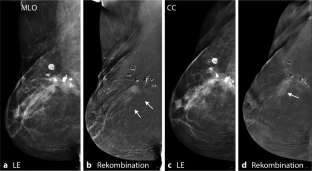

Abb. 2